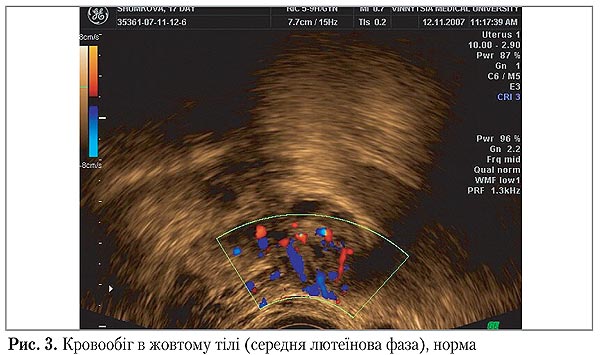

Слід зазначити, що одразу після овуляції у здорових жінок залишалися високі значення МСС, протягом 4–5-ти днів (рання лютеїнова фаза) відносно стабільними величини ІР (0,44–0,45). Кровообіг в жовтому тілі у таких жінок становив 70–100% його окружності (рис. 3).